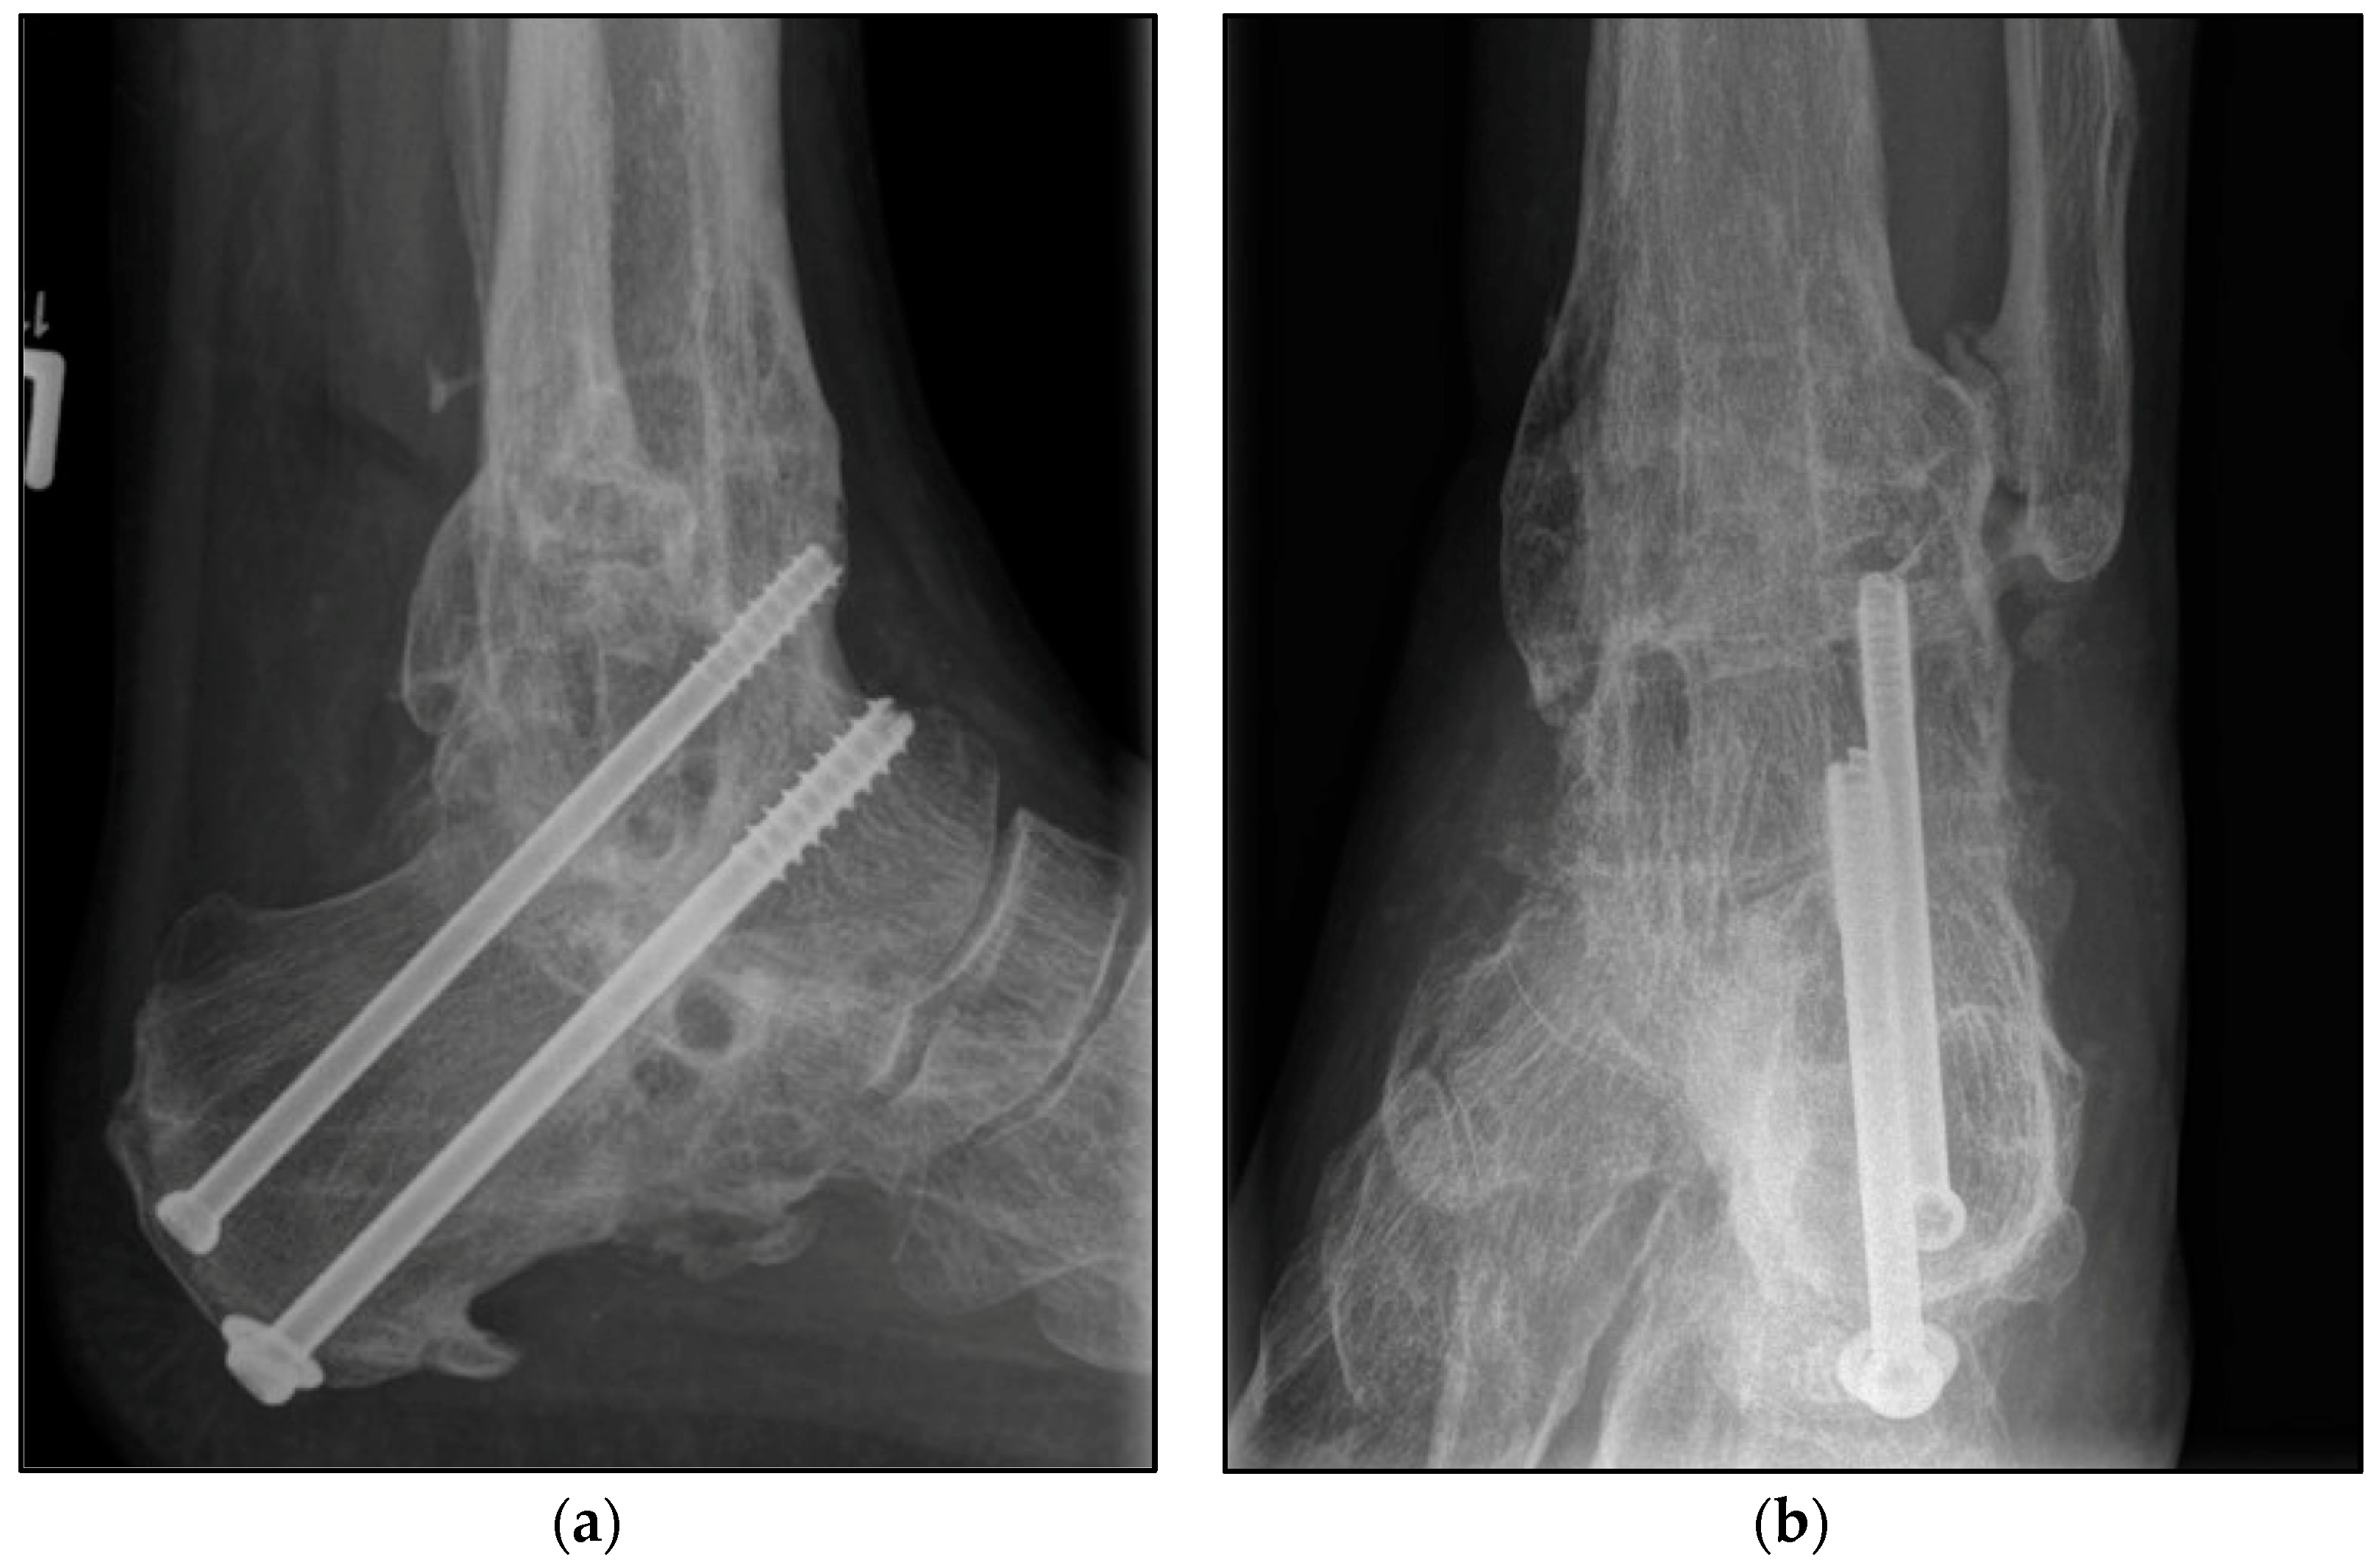

Figure 2.

Postoperative radiographic findings of end-stage posttraumatic arthritis of the left ankle with septic history of a 54-year-old male treated with a screw fixation due to nonunion after tibiotalocalcaneal arthrodesis treated with arthrodesis nail. (a,b) Anteroposterior and lateral view; view, 6 years post operation.